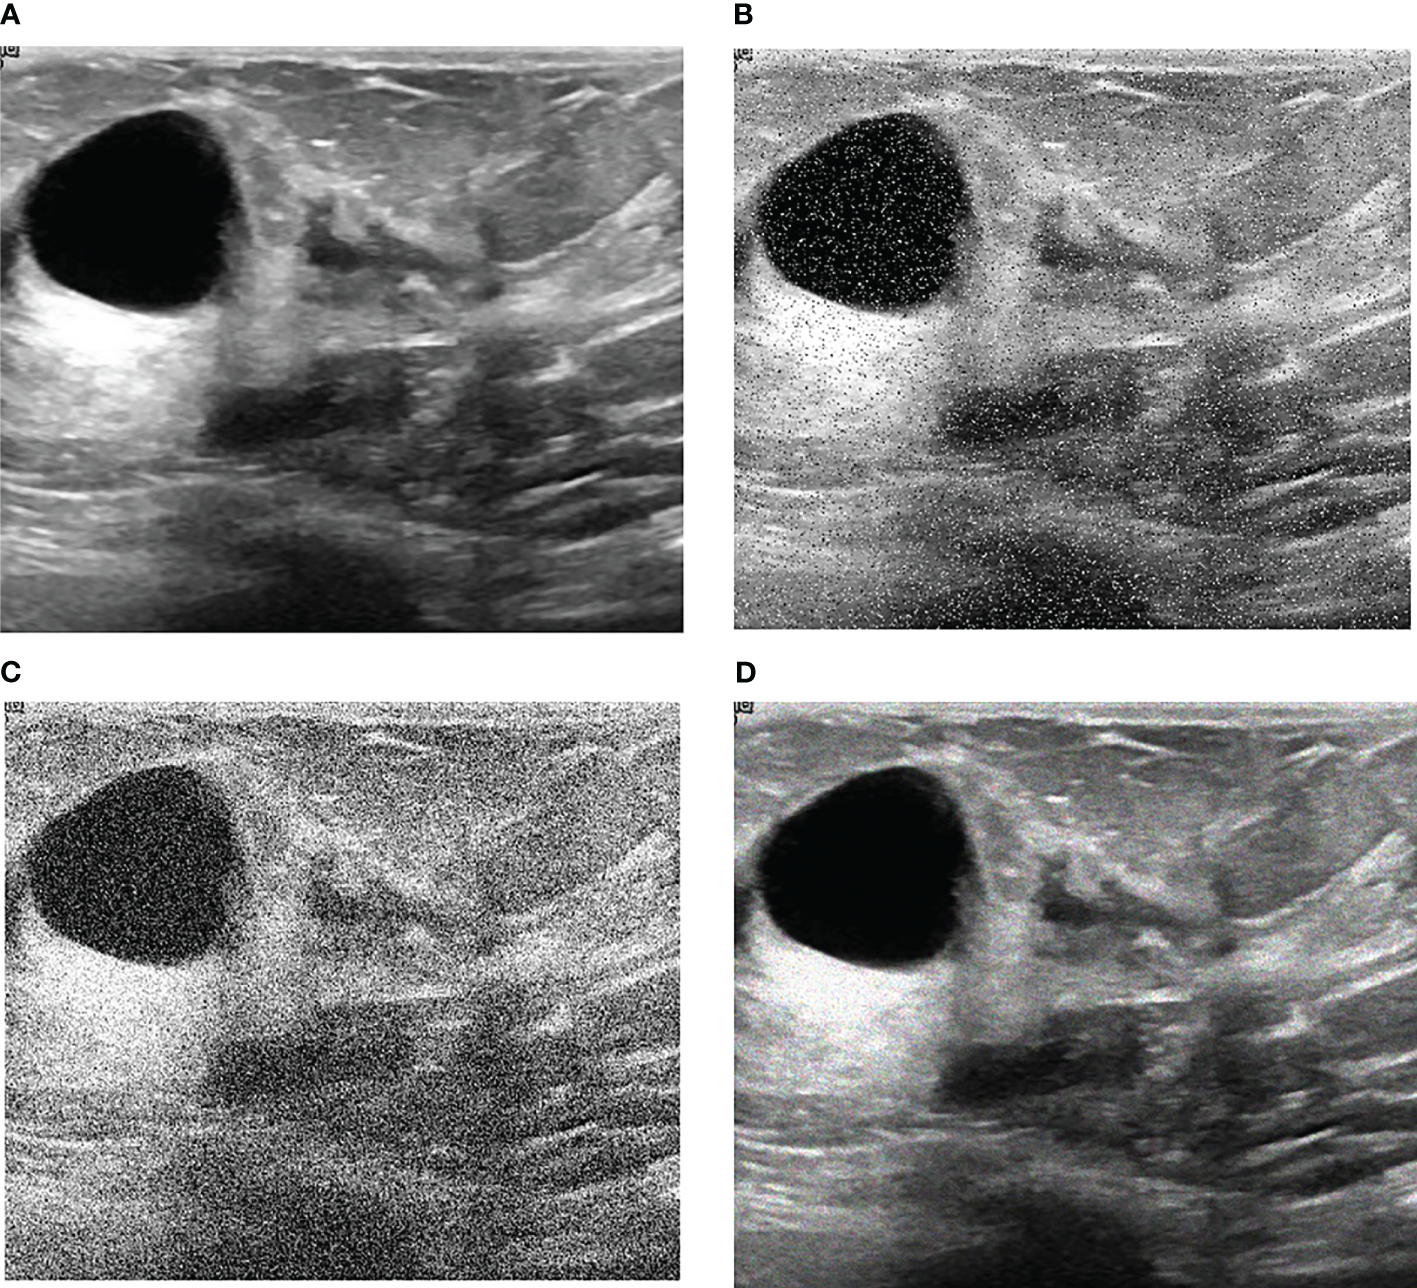

Our research is based on the workflow depicted in the Figure 1 below. Firstly, we used 8617 breast ultrasound images to train nine neural networks introduced in Section 2.3 and evaluated their performance on this benchmark. On the other hand, the part of data enhancement was added in the training. Manoj Gupta et al. explored the various kinds of noises present within the ultrasound medical images and also the filters that are used for the noise removal purpose. They found that the noises were introduced in the ultrasound images are Salt and Pepper Noise, Speckle Noise, Gaussian Noise and Poisson noise (21). For this problem, we choose three kinds of noise, namely Salt and Pepper Noise, Gaussian Noise and Speckle Noise, to directly add to the picture. Noise was added to 60% of the 8617 images, with random intensity Salt and Pepper Noise added to 20% of the images, random intensity Gaussian Noise added to 20% of the images, and random intensity Speckle Noise added to the rest. Afterward, three types of noise, including Gaussian Noise, Salt and Pepper Noise and Speckle Noise, are applied to the test set separately. The ratio of pepper noise to salt noise is fixed at 1:1. The addition level of each noise is 0, 0.02, 0.04,0.06, and so on. For Salt and Pepper Noise, the noise level is the ratio of Salt and Pepper Noise points added in this experiment to replace the noise points in the original figure. And for Gaussian Noise, the level of added noise is controlled by adjusting the size of the standard deviation of the Gaussian distribution. The larger the standard deviation is, the more noise will be added, and the more severely the image will be damaged. Due to the Speckle Noise does not follow normal distribution and quite close to Rayleigh and Gamma distributions. For Speckle Noise, the level of added noise is controlled by adjusting the size of the standard deviation of the Gamma distribution. The ultrasound image of the breast with three kinds of noise added and the original image are shown in Figure 2.

Figure 2

Noise impact on breast ultrasound images. (A) Original Image. (B) Salt & Pepper Noise. (C) Gaussian Noise. (D) Speckle Noise.